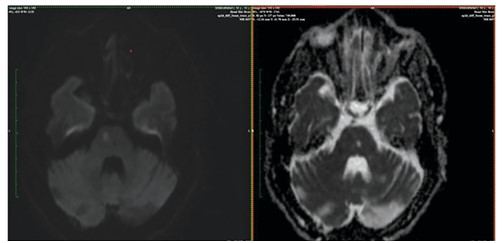

Pathological Laughter as a Manifestation of Left Frontal and Right Pons Stroke

Background: Pathological laughter is a disorder of emotional expression characterized by bouts of uncontrollable laughter with no motivating factor. It is seen in various neurological disorders such as Post Traumatic Brain injury, Post stroke, Multiple sclerosis, Amyotrophic lateral sclerosis, etc. Case Summary: Here, we present a case of a 46 year old male who presented with pathological laughter to the psychiatry outpatient department following acute infarct in the left frontal and right pons area of the brain. Discussion: Our patient had developed pathological laughter subsequently after right pons and left frontal infarct as pseudobulbar affect. Our case report is unique as both the voluntary and involuntary pathways mediating laughter are involved. Conclusion: Hence, our case may be indicative of possible role of combination of antipsychotics and antidepressants, which warrants further research.